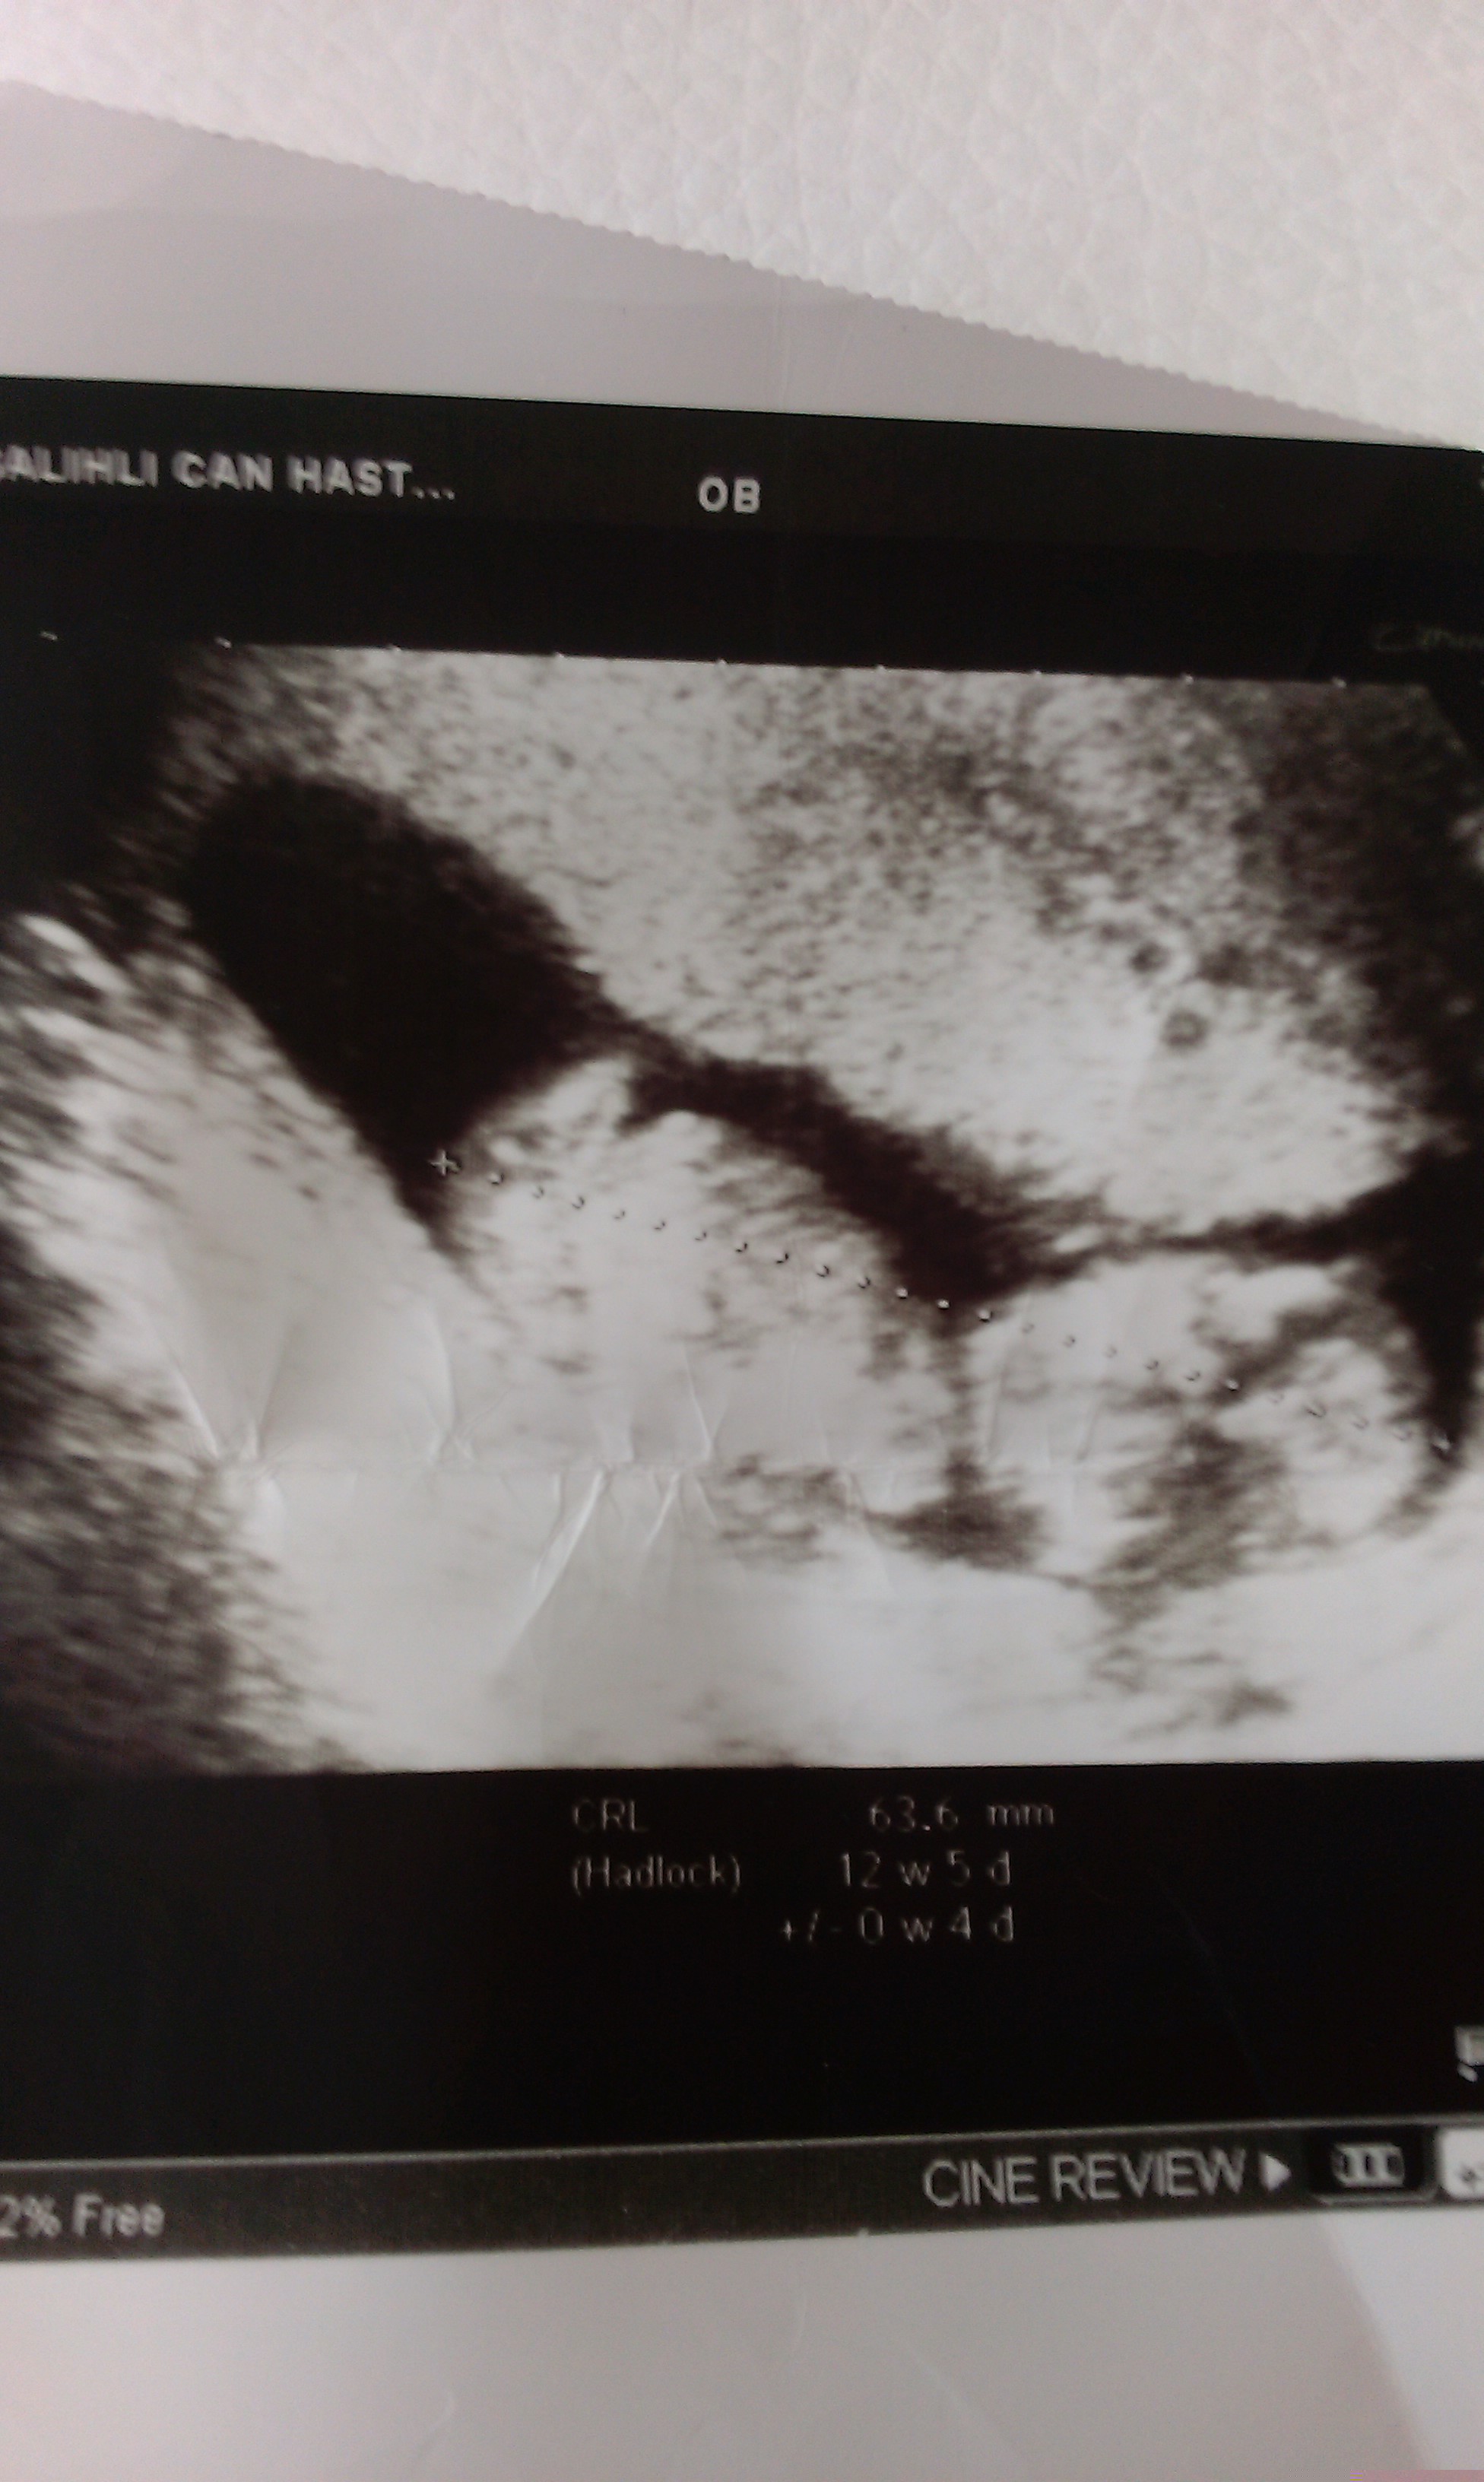

Günaydın kızlar bu da benim miniğim, :) cinsiyet yorumları bekliyorum :) geçen hafta 31 mart salı günü ikili test randevumda 13. haftanın içindeydik, anca bugün yükleyebildim fotosunu. benim hafta döngüm cumadan cumaya :)

çok teşekkür ederim canım, inşallah sağ selamet alırız bebeklerimizi kucaklarımıza. hayırlısı olsun inşallah :) , ultrason görüntüsünü baya evirdi çevirdi gösterdi, ama tam net değil tabiki, ultroson fotoğrafı siyah beyaz tonlamalarında demi, bacak arasını gösterdiğinde yan yana iki tane beyaz nokta vardı, erkek mi kız mı artık kesin olarak nisanın son haftası belli olacak :)